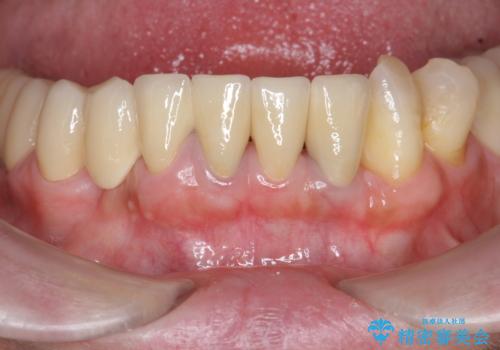

歯周病 全顎治療

歯周病全顎治療について

全体的な歯周病が認められる場合、歯を失った一部のみの治療となることはほぼありません。

失ってしまった機能を回復し、今後歯を失わないよう残せる歯に歯周病治療を行い、安定した咬合を確立することで長期的に問題なく噛めるような口腔内環境を達成できるようになると考えます。